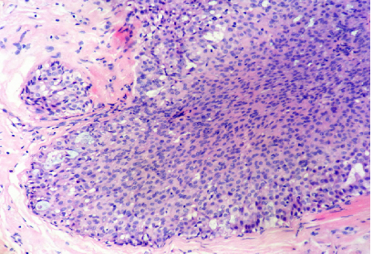

结构特点:轮廓清楚的实性结节纤细的血管轴心。

纤细的血管轴心周围细胞呈栅栏状排列

特征性细胞:形态多样,卵圆形,梭形,多边形,印戒样或浆细胞样胞浆嗜酸性颗粒状,单形性,核低至中级别,染色细腻,可见小核仁核分裂少见(<5/10HPF)肿瘤细胞可有细胞内、外粘液形态单一,呈圆/卵圆形,胞浆淡染、嗜酸性颗粒状嗜酸性颗粒状

SPF细胞形态